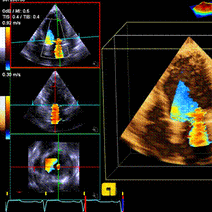

- 超声心动图入门,,,一、切面超声心动图二维超声图像一探测部位心前区胸骨左缘肋间,心脏裸区心尖区在左侧心尖搏动处探查胸骨上窝利于大血管及心底各结构显示剑突下利于肺气肿,小孩,垂直位心脏探查,,,主要切面有,,,二常见图像左室长轴观探头位于左肩

- 超声心动图正常心脏声像图先天性心脏病超声诊断心脏瓣膜病超声诊断心肌病超声诊断冠心病、心脏肿瘤、心包疾病超声诊断内容概述先天性心脏病心脏瓣膜病心肌病冠状动脉粥样硬化性心脏病心脏肿瘤和血栓心包疾病禁忌症适应症概述探头频率成人儿童检查前准备无需特

超实用!7 步读懂超声心动图 丁香园